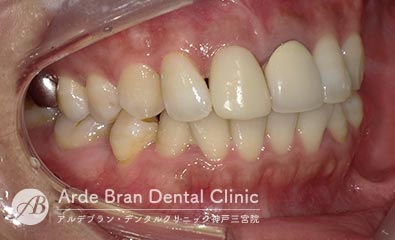

- ジルコニアセラミッククラウン(20代 女性 治療期間1カ月)

- 他院で入れた前歯の被せ物の形態や色調が隣の歯と合っていないため、やり替えたいとの事でご来院されました。切端に透明感があり、歯頚部から歯冠部にかけてグラデーションがある難しい歯でしたがトップテクニシャンとの連携により見事に再現する事が出来ました。

- 治療前

- 治療後

| 治療方法 | ジルコニアセラミッククラウンによる審美歯科治療 |

|---|---|

| 治療本数 | 2本 |

| 治療期間(通院回数) | 1カ月(4回) |

| 費用 | ジルコニアセラミッククラウン 24万円+TAX 仮歯 6千円+TAX |

| リスク副作用 | 審美歯科治療に関するリスクや副作用について、詳しくはこちらをご参照ください。 |